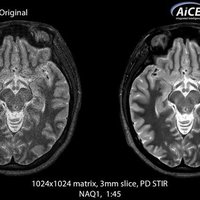

KI-optimiertes Arbeiten und modernste 3T-Technologie machen den Vantage Galan 3T von Canon Medical aus. Canons KI-Anwendung AiCE, kurz für Advanced intelligent Clear-Imagequality Engine, entfernt intelligent das Rauschen und führt zu einer Verbesserung des SNR (Signal-Rausch-Verhältnis). Mit Hilfe der Deep Learning Technologie gelingen besonders klare und deutliche Bilder. Insgesamt ermöglicht die KI-Unterstützung des Vantage Galan 3T somit nicht nur eine höhere Auflösung der Bilder, sondern verkürzt in vielen Fällen auch die Aufnahmezeit.

• AiCE KI-Technologie zur Entfernung von Bildrauschen und Verbesserung des SNR